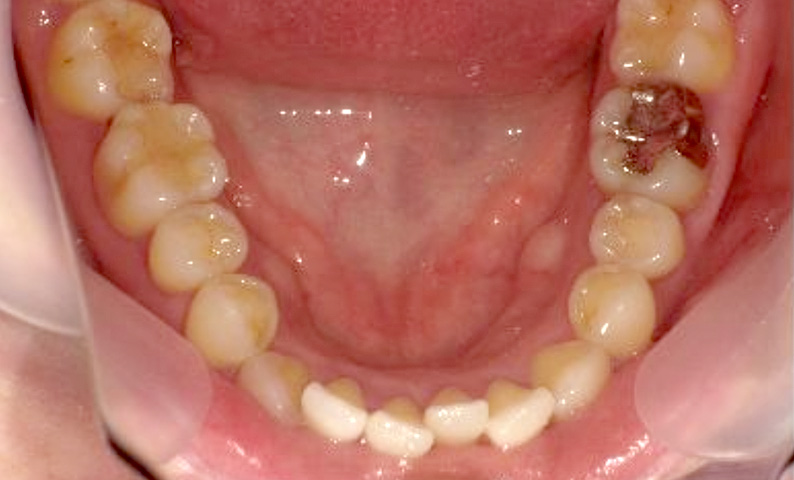

症例_002 下顎だけの部分矯正

治療期間:6ヶ月金額:21万円+税女性前歯のデコボコ下の前歯だけ

| Before | After |